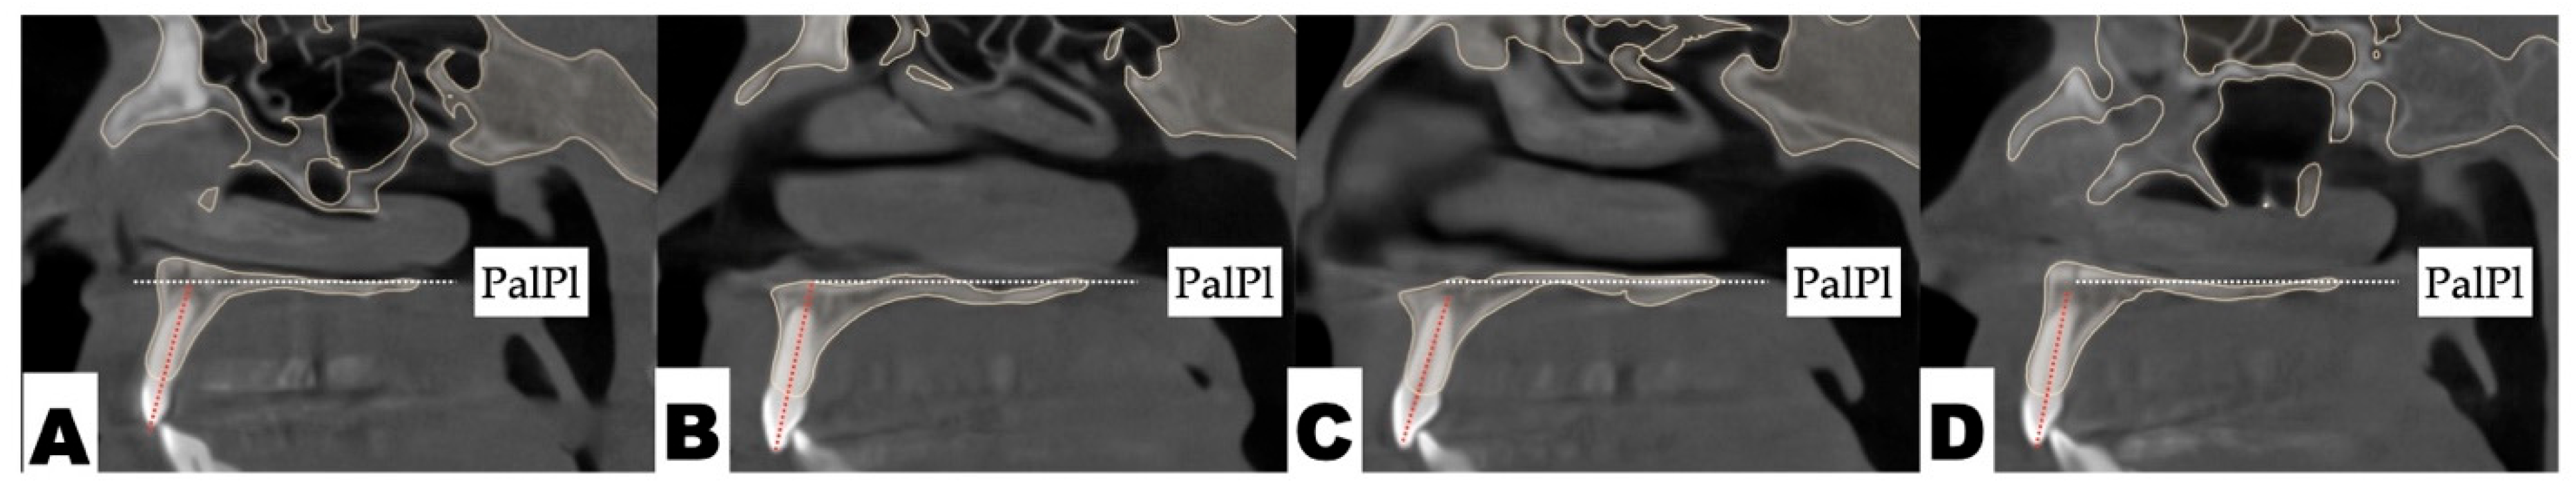

2.3.3. Osteotomy Planning and Appliance Design

2.3.4. Postoperative Assessment, Outcome Analysis, and Asymmetry Correction